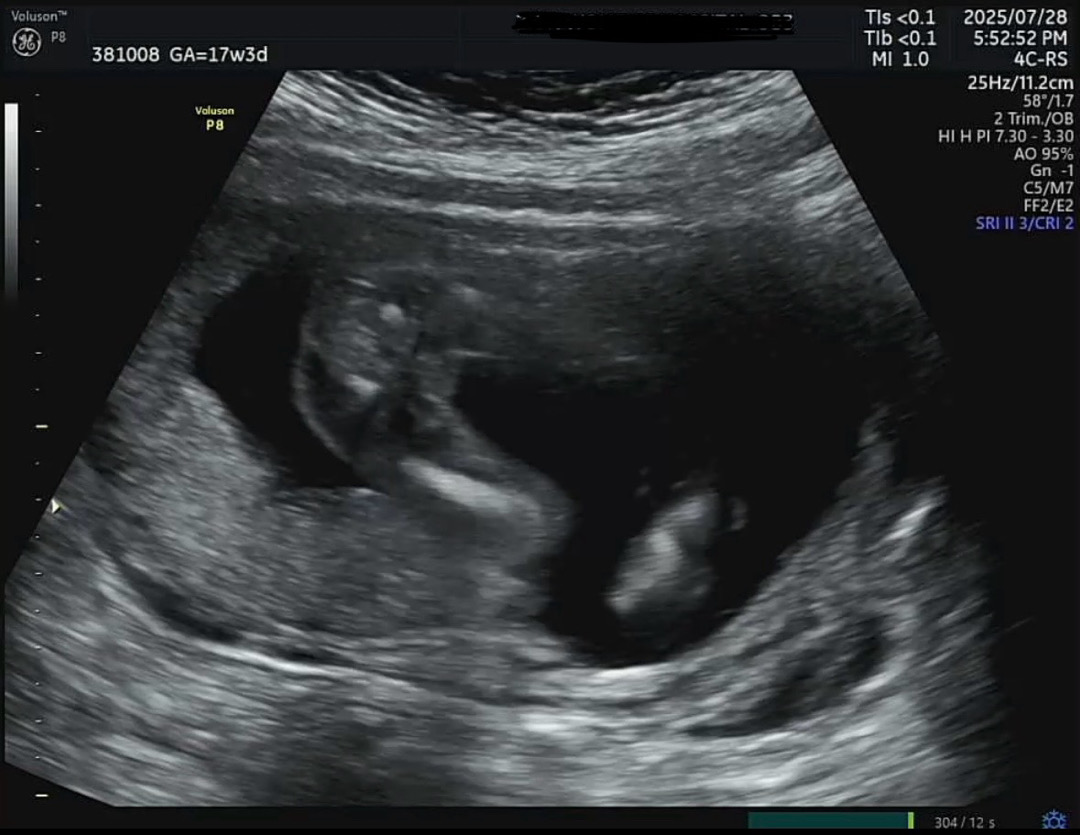

성별 오때보이나요?

다리사이 초음파인데 성별 한번 봐쥬세요!!! 초산모라 잘모르겠어요ㅠ

17주에요

그 주수면 딸같아요! 제 애기 초음파 다리사이랑 비슷해요ㅎㅎ